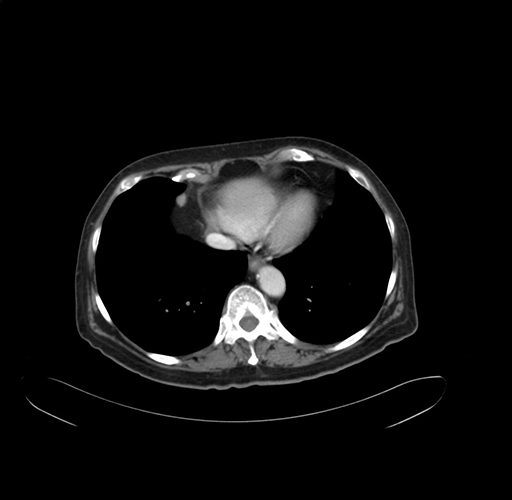

Pre-Chemo: Axial Venous

Axial Venous